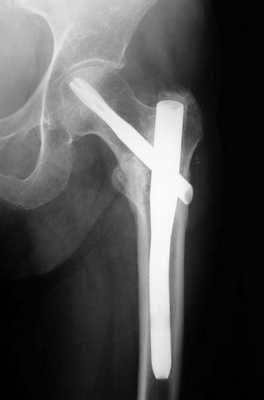

Остеосинтез ТБС на рентгене

Остеосинтез при переломе шейки

При ПШБ в основном проводится внутренний (погружной) остеосинтез. То есть, специальная фиксирующая конструкция соединяется непосредственно с костными структурами после оперативного обнажения места перелома. В ортопедии применяют два вида внутреннего соединения репонированных отломков:

- интрамедуллярный (внутрикостный);

- экстрамедуллярный (накостный).

Интрамедуллярный метод

При интрамедуллярной технике дистальный и проксимальный отломки соединяются специальными стержнями или штифтами, проведенными через костномозговой канал каждого из них. Сегодня преимущество на стороне эндосистем блокирующего типа. На их противоположных концах имеются уже готовые отверстия для винтов или своеобразные загибы, повышающие степень стабилизации системы. Интрамедуллярными устройствами, которые бывают ригидными или полуэластичными, возможно зафиксировать даже множественные осколки.